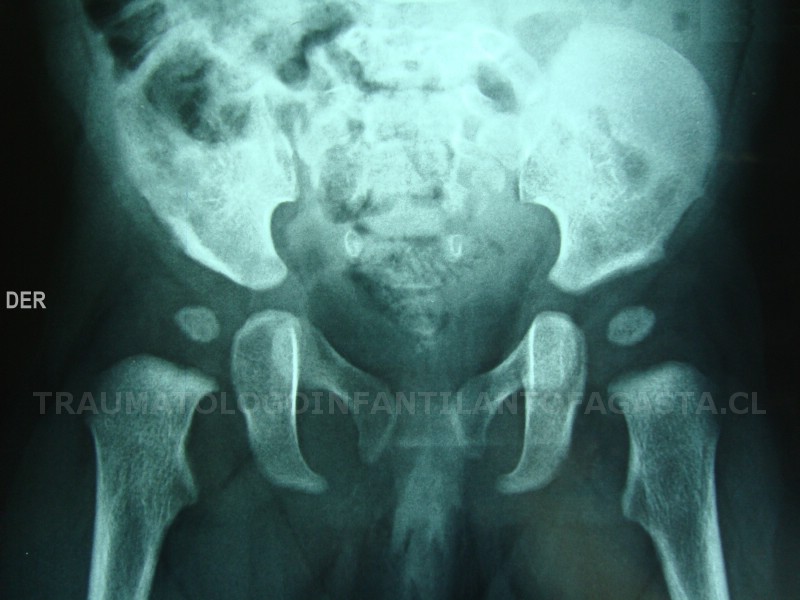

Epifisiolisis de cadera